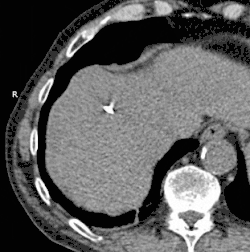

Animated GIF showing cryoablation of mass in right liver lobe using two probes. Time elapsed is approximately 30 minutes.